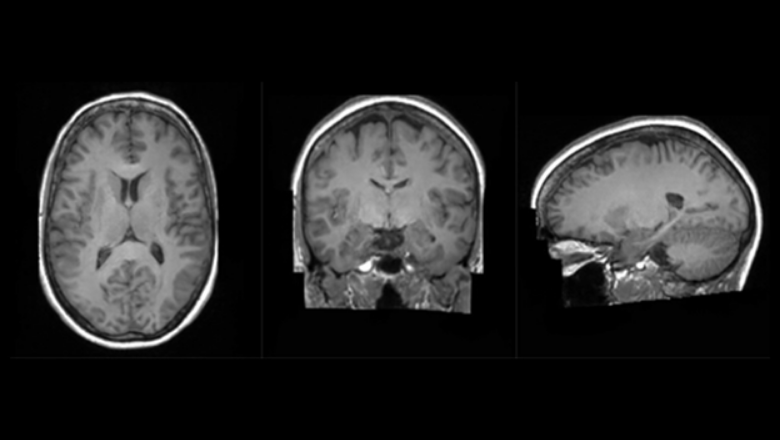

The Synthetic Brain Project focuses on building deep learning models that can synthesise artificial 3D MRI images of human brains. These models can help scientists understand what a human brain looks like across a variety of ages, genders, and diseases.

The aim of developing the AI models, using the Cambridge-1 supercomputer, is to help diagnose neurological diseases based on brain MRI scans, but it may also be used to predict diseases that a brain may develop over time and enable preventative treatment.

The use of synthetic data has the additional benefit that it can ensure patient privacy since the images were generated, enabling the research to be opened up to the wider UK healthcare community.

“We can ask our models to generate an almost infinite amount of data, with prescribed ages and diseases; with this, we can start tackling problems such as how diseases affect the brain and when abnormalities might exist.”